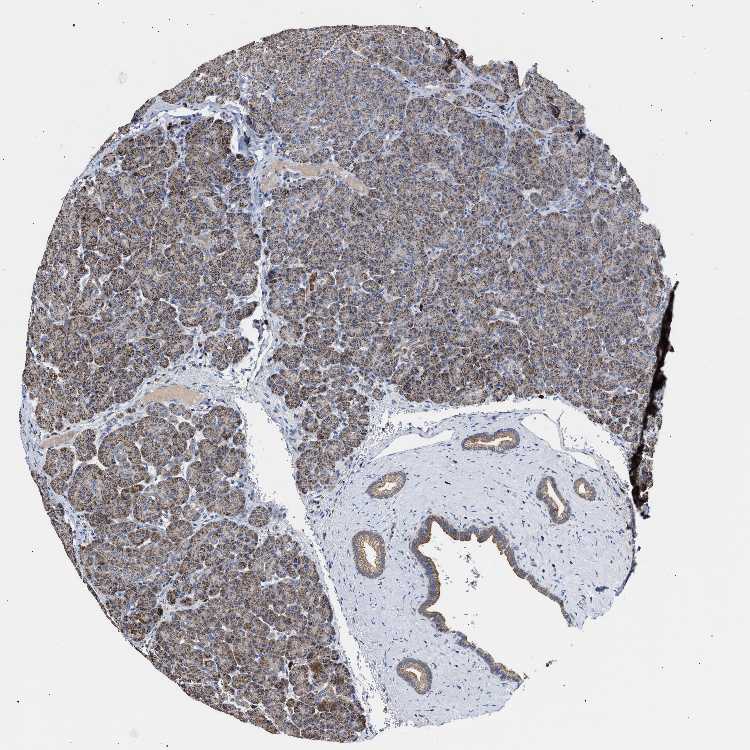

PANCREAS - Antibody stainingi

Antibody staining in the annotated cell types in the current human tissue is reported as not detected, low, medium, or high, based on conventional immunohistochemistry profiling in selected tissues. This score is based on the combination of the staining intensity and fraction of stained cells.

Each image is clickable and will lead to virtual microscopy that enables deeper exploration of all samples and also displays staining intensity scores, fraction scores and subcellular localization as well as patient and tissue information for each sample.

Antibody HPA020081Antibody HPA020103Antibody HPA029476Antibody CAB068194

Exocrine glandular cells HighMediumLowHigh

Pancreatic endocrine cells MediumLowNot detectedMedium